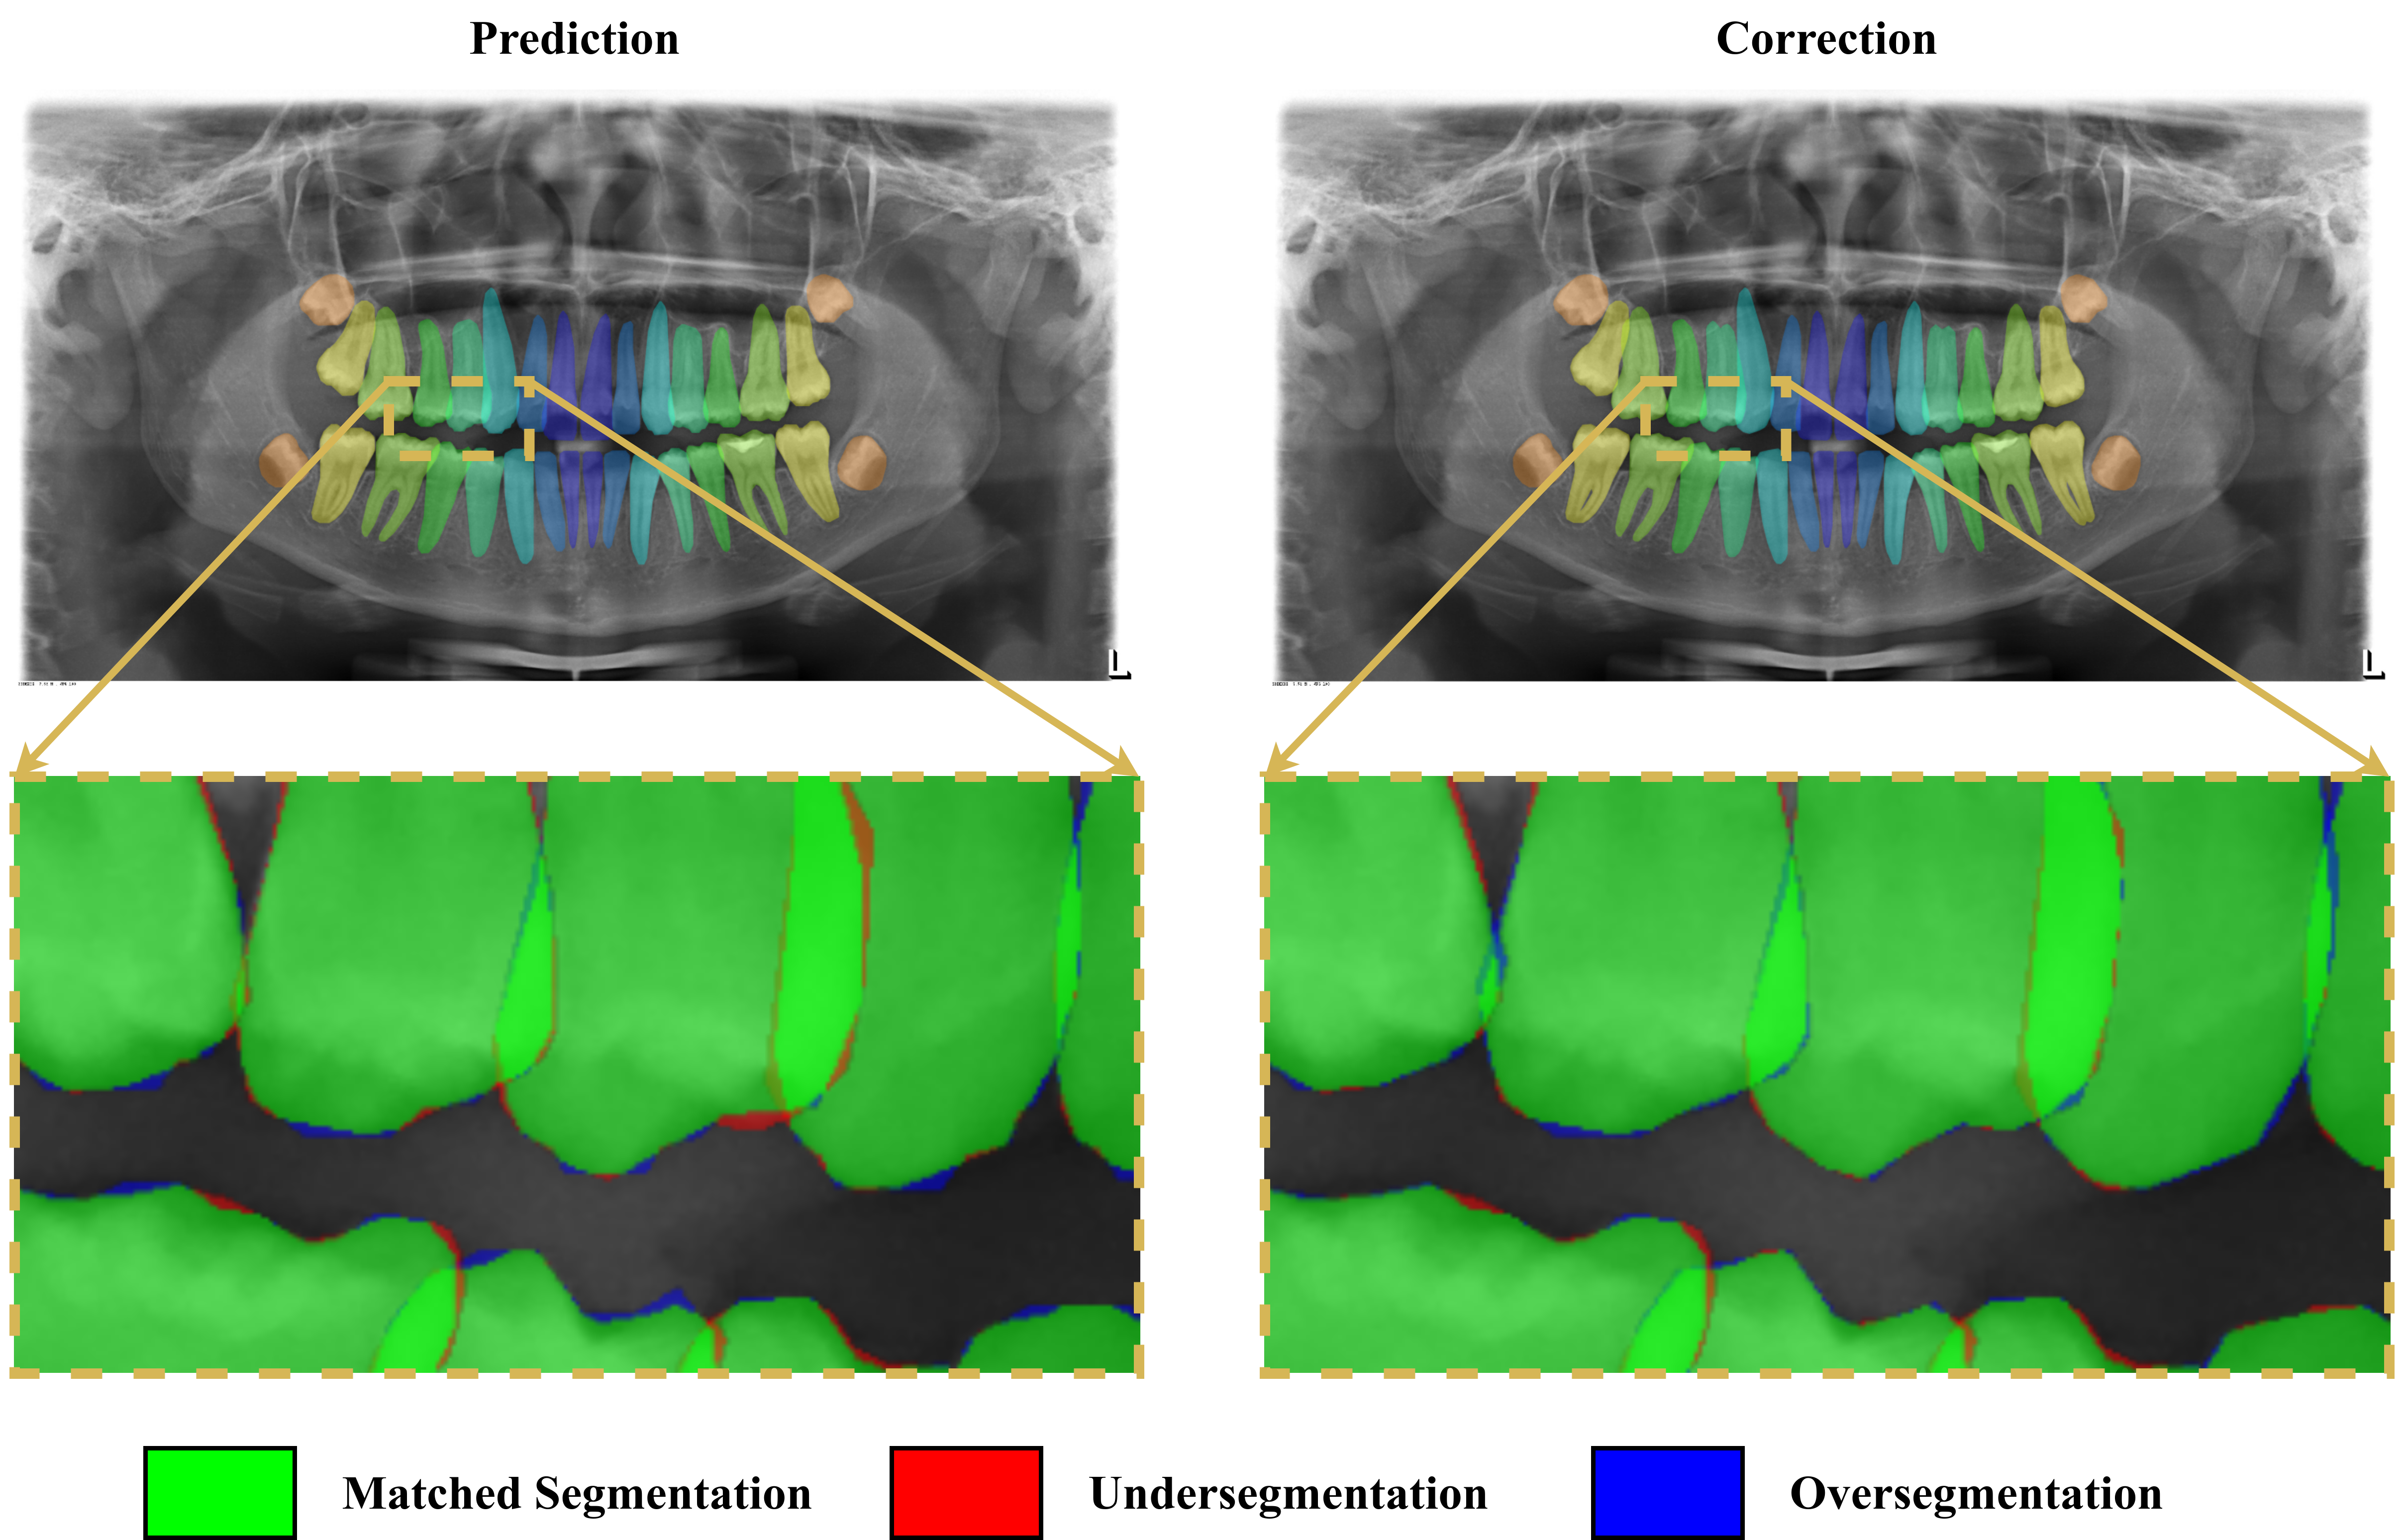

3.7 Qualitative analysis

The quantitative analyses guided our qualitative analyses. We focused on the best and worst results according to the primary metric, comparing the ground truth with the network predictions and the verified labels. Figures 12 (a) and (b) illustrate the best and the worst HTC 4’s results, respectively, according to the segmentation mAP on the test data set. Figure 12 (a) corresponds to a well-focused, crisp and clear radiograph from a 32-teeth healthy mouth, characteristics common to the best results. From the zoomed area, we see that the annotation correction led to a final label closer to the ground truth and also less noisy.

The worst result, illustrated in Figure 12 (b), came from a slightly blurry image from an unhealthy mouth, a common pattern in the radiographs of the worst results. However, in this case, the network performance was reasonably good, and the low metric was due to main factors. First and most important, the annotator wrongly labeled the teeth 32, 33, 34 and 35 respectively as teeth 31, 32, 33 and 34, probably due to a sequence of typos, which reduced the segmentation mAP significantly. Second, the presence of radiolucent material prostheses and restoration encumbered the segmentation task for both model and annotator. The zoomed area shows that model undersegmented those spots, which were adjusted by the annotator, but still missed some areas. The other annotation corrections smoothed the noisy borders and reduced the difference from the ground truth labels. We additionally illustrate in Figure 12 (c) a sample result on a mixed dentition mouth. These radiographs are challenging for models and human annotators due to overlapping. In this particular image, there are also occlusions between posterior teeth, hardening the task. However, the model prediction proved to be adequate, even before the labeling verification. The zoomed area shows that the corrections reduced the gap to the manual ground truth labels, but there were some divergences for root segmentation of teeth 54 and 55.

Refer to caption

(a) HTC 4’s best result, which happened on a well-focused, crisp and clear radiograph from a 32-teeth healthy mouth, characteristics common to the best results.

(b) HTC 4’s worst result, which happened on a slightly blurry radiograph from an unhealthy mouth with radiolucent material prostheses.

(a) Sample of HTC 4’s results on a mixed dentition radiograph.

Figure 12: HTC 4’s best and worst results according to the segmentation mAP on the test set, and an additional result sample on a mixed dentition radiograph. The illustrations compare the predictions before and after the corrections by the annotators. The zoomed areas highlight the matched segmentation, undersegmentation, and oversegmentation with the ground truth labels, evincing that the corrections led the final labels to be less noisy and closer to the ground truth.